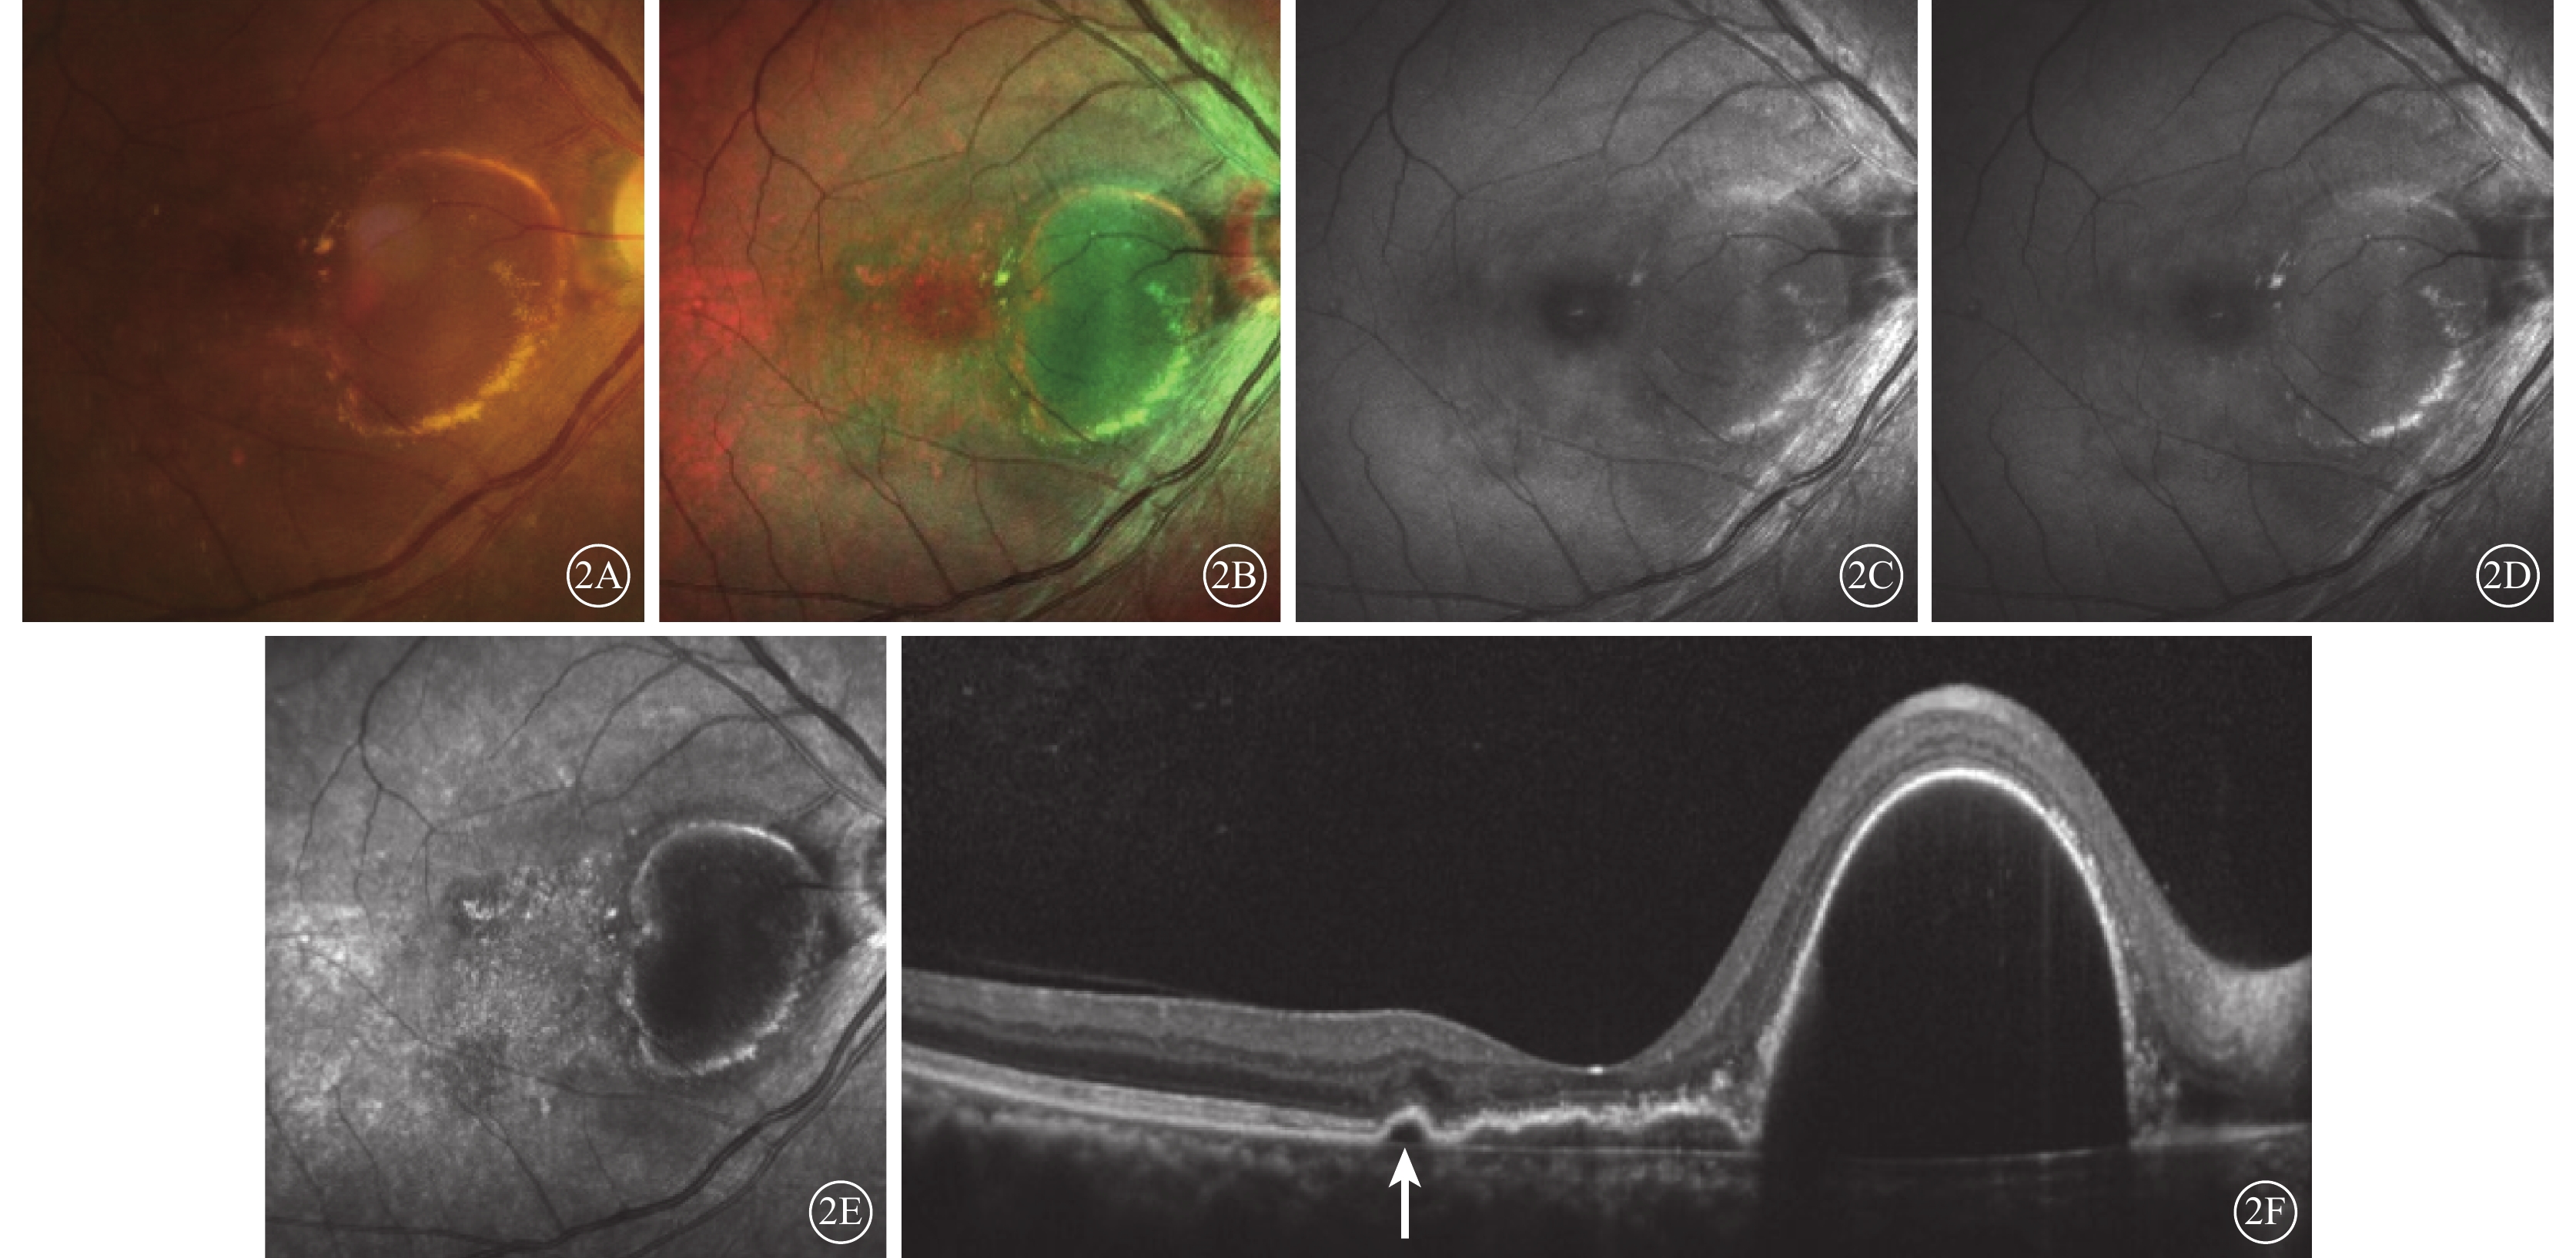

典型的漿液性PED在眼底彩色照相中表現為圓形或橢圓形的病灶,顏色較周圍正常視網膜組織偏暗,可伴黃白色滲出(圖2A);在cSLO成像中表現為圓形或橢圓形的綠色病灶(圖2B~2E),藍光反射、綠光反射中病灶稍弱反射,紅外反射中病灶反射最弱,與HD-OCT觀察到的PED位置一致(圖2F)。

典型的漿液性PED在眼底彩色照相中表現為圓形或橢圓形的病灶,顏色較周圍正常視網膜組織偏暗,可伴黃白色滲出(圖2A);在cSLO成像中表現為圓形或橢圓形的綠色病灶(圖2B~2E),藍光反射、綠光反射中病灶稍弱反射,紅外反射中病灶反射最弱,與HD-OCT觀察到的PED位置一致(圖2F)。

本研究結果顯示,PCV的漿液性PED在cSLO偽彩圖中表現為綠色或深綠色病灶,在紅外反射中呈現明顯弱反射暗區,藍光反射和綠光反射較弱。該觀察結果與Tan等[10]描述一致。而出血性PED則表現為深紅色病灶,綠光反射、藍光反射和紅外反射均呈現明顯弱反射。因為激光成像的原理是依靠不同波長激光而獲得不同層次的視網膜成像,藍光反射、綠光反射和紅外反射分別呈現視網膜淺層、中層和深層的結構。炫彩成像的過程中,依據眼底不同病變對不同波長的激光吸收、反射和透射的程度不同,顯示為相應波長激光反射的綜合圖像:藍光反射強度對應藍色成分,綠光反射強度對應綠色成分,而紅外反射強度對應紅色成分,3種反射的相對強弱決定病灶的顏色。水對光譜中的紅外部分表現出強烈的吸收,因而積液、水腫在紅外反射圖像中顯示為明顯的弱反射。因此,漿液性PED在紅外反射中呈現明顯暗區。紅外光被吸收多,反射弱;藍光和綠光吸收少,反射相對較強。并且,PED向視網膜內層隆起,病灶位于綠光反射區間,因此漿液性PED呈現綠色。血液對420~575 nm的光譜吸收率最高,反射弱;而紅外光吸收率最低,反射強[11]。因此,出血性PED在藍光反射和綠光反射出現明顯弱反射;炫彩成像中,藍光、綠光吸收多,反射弱;紅外光吸收少,相對反射較強,因此呈現紅色病灶。

本研究結果顯示,PCV的漿液性PED在cSLO偽彩圖中表現為綠色或深綠色病灶,在紅外反射中呈現明顯弱反射暗區,藍光反射和綠光反射較弱。該觀察結果與Tan等[10]描述一致。而出血性PED則表現為深紅色病灶,綠光反射、藍光反射和紅外反射均呈現明顯弱反射。因為激光成像的原理是依靠不同波長激光而獲得不同層次的視網膜成像,藍光反射、綠光反射和紅外反射分別呈現視網膜淺層、中層和深層的結構。炫彩成像的過程中,依據眼底不同病變對不同波長的激光吸收、反射和透射的程度不同,顯示為相應波長激光反射的綜合圖像:藍光反射強度對應藍色成分,綠光反射強度對應綠色成分,而紅外反射強度對應紅色成分,3種反射的相對強弱決定病灶的顏色。水對光譜中的紅外部分表現出強烈的吸收,因而積液、水腫在紅外反射圖像中顯示為明顯的弱反射。因此,漿液性PED在紅外反射中呈現明顯暗區。紅外光被吸收多,反射弱;藍光和綠光吸收少,反射相對較強。并且,PED向視網膜內層隆起,病灶位于綠光反射區間,因此漿液性PED呈現綠色。血液對420~575 nm的光譜吸收率最高,反射弱;而紅外光吸收率最低,反射強[11]。因此,出血性PED在藍光反射和綠光反射出現明顯弱反射;炫彩成像中,藍光、綠光吸收多,反射弱;紅外光吸收少,相對反射較強,因此呈現紅色病灶。